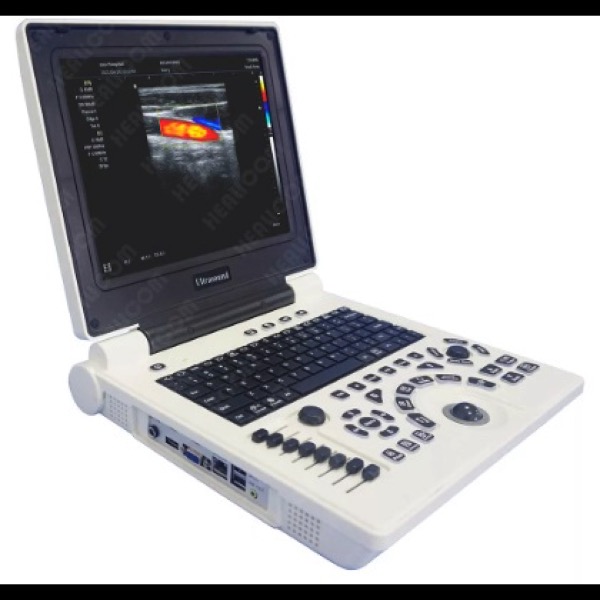

Écran couleur haute résolution de 12 pouces, 2 ports Sondes activés.

Modes d image :B,B/B,4B,B+M,CFM,B+CFM,PDI,B+PDI,PW

Applications cliniques : Abdomen, cardiologie, obstétrique, gynécologie, urologie, pédiatrie, petits organes,cardiaque.

Technologie imagerie:THI

Batterie rechargeable 3200mAh

Interfaces,HDMI,VGA,DICOM,USB,sortie video

Echelle de gris 256 niveaux